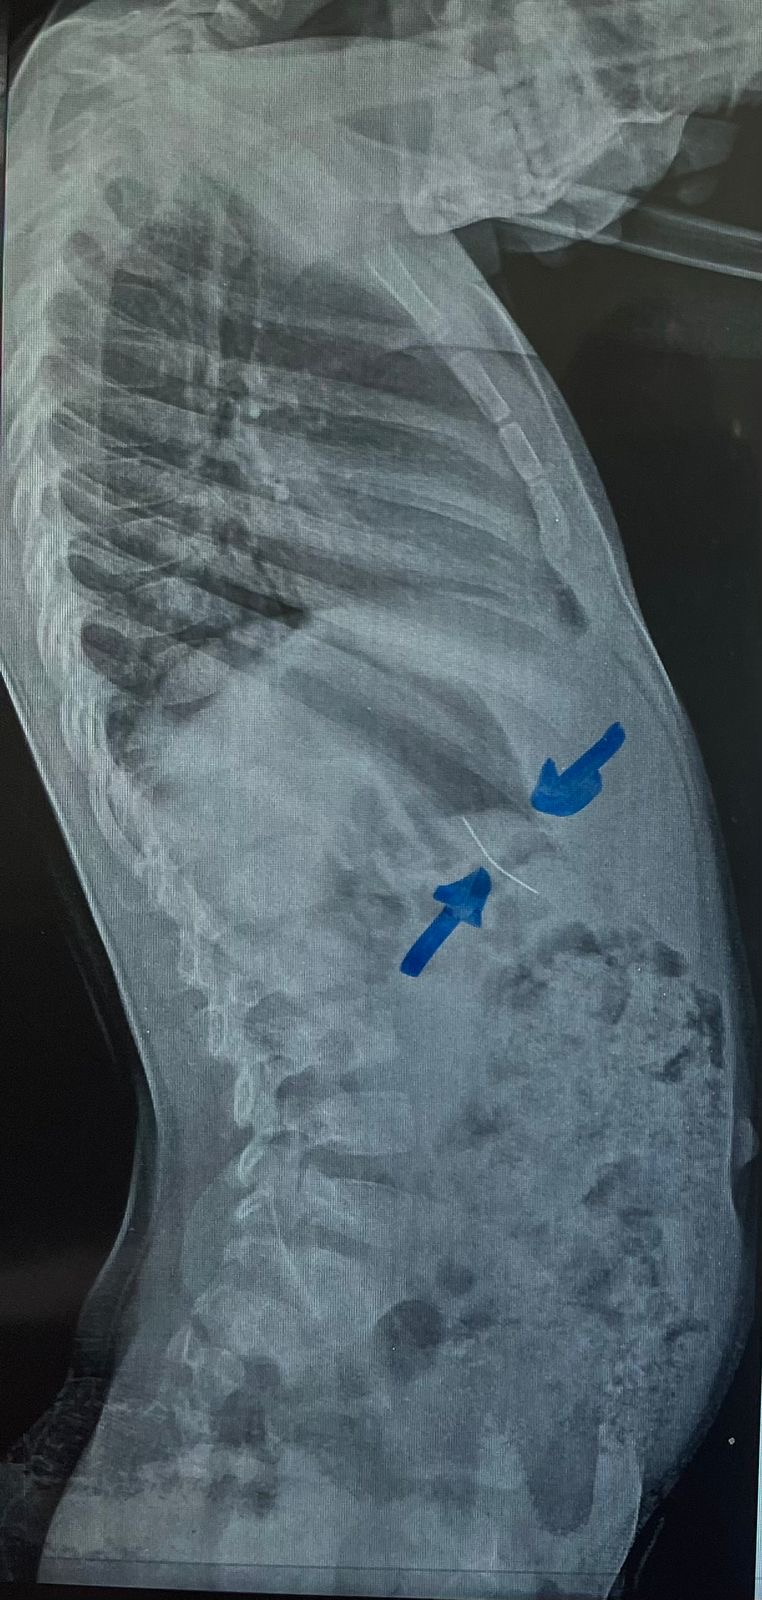

نجح فريق طبي من وحدة أمراض الجهاز الهضمي والكبد ومناظير الأطفال بقسم طب الأطفال بمستشفى جامعة سوهاج، في إجراء تدخل دقيق لاستخراج دبوس من معدة طفل يبلغ من العمر أربع سنوات، بإستخدام منظار معدة خاص بالأطفال، دون حدوث أي مضاعفات، وقد غادر الطفل المستشفى بعد ثلاث ساعات فقط من الإجراء، وهو في حالة صحية جيدة.

وأكد الدكتور أحمد كمال، المدير التنفيذي للمستشفيات الجامعية جامعة سوهاج، أن التعامل مع الحالة تم بسرعة وكفاءة، حيث تمكن الفريق الطبي من استخدام المنظار الخاص بالأطفال لاستخراج الدبوس دون أي تدخل جراحي، مما ساهم في خروج الطفل من المستشفى في نفس اليوم بحالة ممتازة.